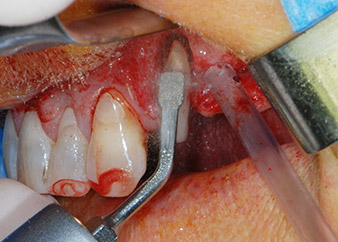

Einen Monat nach dem Eingriff waren sowohl die Schmerzen als auch die Entzündung an Zahn 24 minimal, die Zahnbeweglichkeit lag jedoch noch bei Miller-Klasse 2. Nach Freilegung und Reinigen des infizierten periapikalen und periradikulären Gewebes wurde das Ausmaß des Knochendefizits deutlich (Abb. 2 und 3).

kompletter Verlust von Knochen und Attachment

Abb. 2 und 3: Bei der Freilegung einen Monat nach endodontischer Revision und Beginn einer systematischen Parodontalbehandlung weist die bukkale Wurzel des Zahns 24 einen kompletten Verlust von Knochen und Attachment auf.

Zunächst wurde in einem Versuch, das Paro-Endo-Problem zu lösen, an der verbleibenden Wurzeloberfläche ein vorsichtiges Debridement mit einem piezochirurgischen Gerät vorgenommen (Piezomed, W&H) (Abb. 4); dann wurde der Apex mit dem gleichen Instrument im Sinne einer WSR abgetragen, um das verbleibende infizierte apikale Gewebe zu entfernen (Abb. 5). Eine retrograde Füllung war nicht notwendig, da die orthograde Füllung gerade revidiert worden war.

Abb. 4: Um den Zahn 24 als vorläufigen Brückenpfeiler zu erhalten, wird das Parodont mit einem piezochirurgischen Sytem gereinigt ...